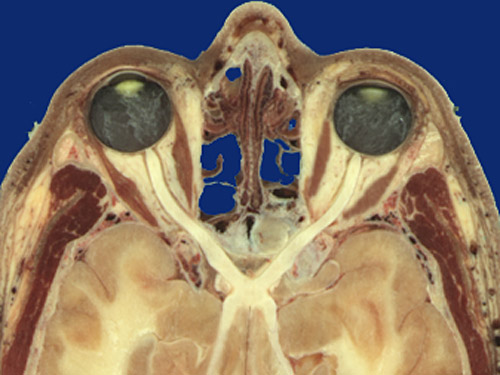

Identify the following regions in the image above: Nasal bone - Frontal process of maxilla - Perpendicular plate of ethmoid - Retrobulbar fat pad - Medial rectus - Lateral rectus - Levator palpebrae superiorus - Temporalis - Optic nerve - Optic chiasm - Optic tract - Zygomatic bone - Posterior chamber with vitreous - Crystalline lens